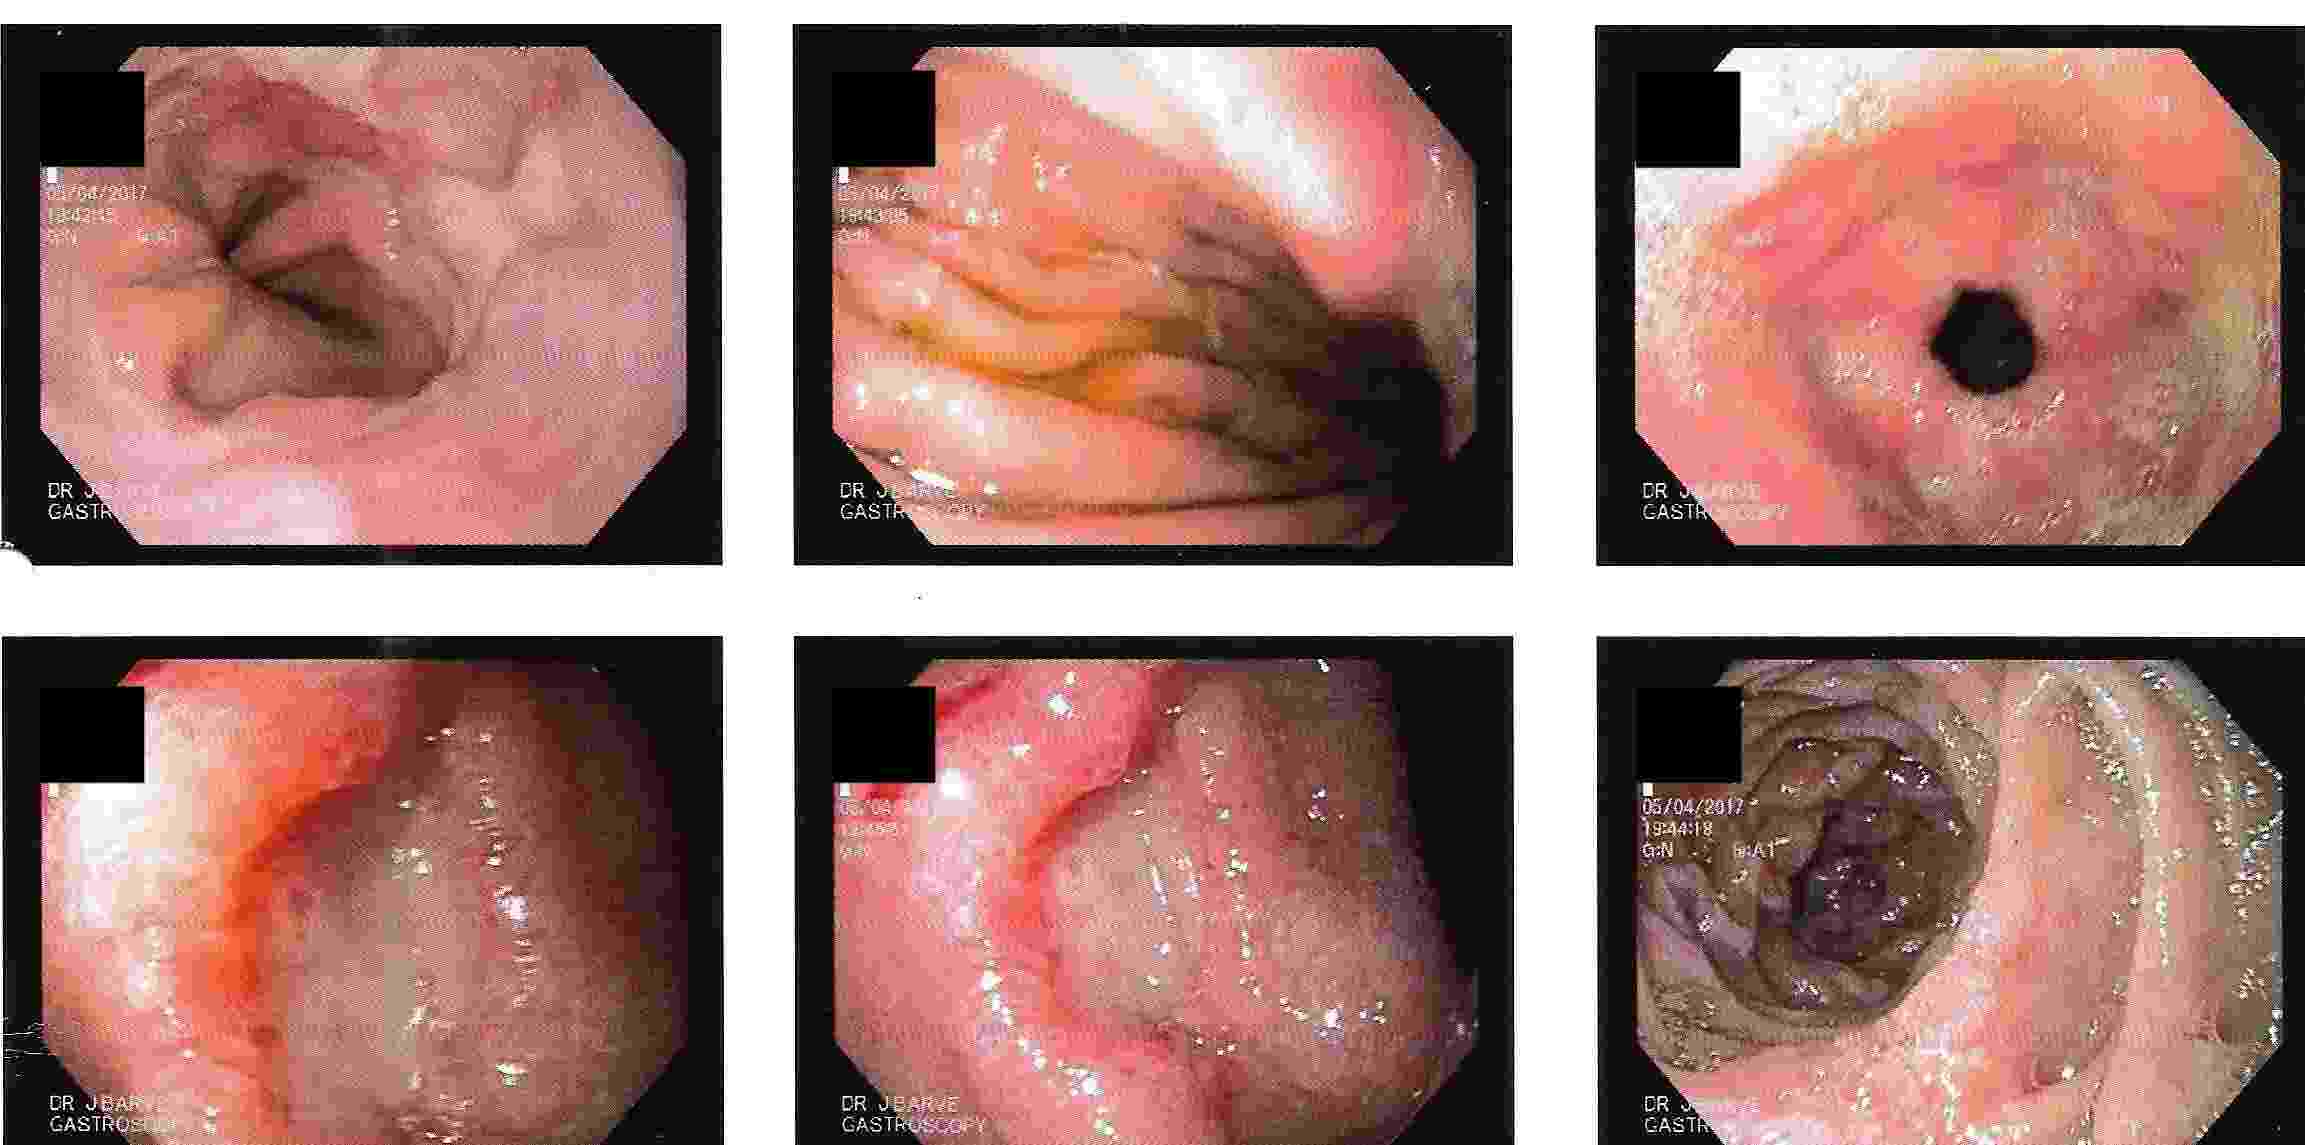

A. UPPER GI ENDOSCOPY popularly known as GASTROSCOPY.

This is done commonly as an out patient procedure with mild sedation without anaesthesia.

Patient can resume with daily routine within an hour.

But should not drive for 2 hours if patient has received sedation.

This procedure allows diagnosis of diseases of upper Gastrointestinal tract, esophagus, stomach and duodenum.

4. Diagnosis of Hiatus Hernia

5. Vomiting of blood / coffee coloured fluid is a serious symptom which may be due to ulcers, cancer of upper GI tract or due to cirrhosis of liver. These conditions can be accurately diagnosed by gastroscopy and majority of these conditions can be treated by endoscopy without need of surgery.

Vomiting of Blood - Endoscopic Treatment

5. Vomiting of blood can be due to severe acidity, consumption of pain killers or blood thinners, ulcer, cancer, cirrhosis of liver etc..

Correct diagnosis and treatment can be offered to these patients.

This is the beginning of the small intestine and most commonly affected by acidity and ulcer.

It also may be involved in certain cancers of upper GI tract.

Bloating, fullness of abdomen, burping, vomiting, pain or burning in upper abdomen mostly on empty stomach after consumption of chillies,

spices or heavy meals occurring at times during sleep are the symptoms related to duodenum.

Duodenum - Chronic Ulcer

Duodenum - Chronic Ulcer with Bleeding

Vomiting of blood due to ulcer, narrowing of duodenum due to ulcer or cancer can be very effectively treated by gastroscopy.